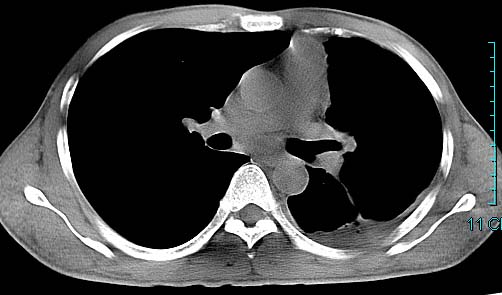

以下是引用ctkz987在2006-3-28 13:04:00的发言:[br]左侧胸腔积液穿刺后多发气液平(多房性),结合临床有高热不除外合并感染。

以下是引用qian在2006-3-28 14:32:00的发言:[br]左肺下叶大片状阴影,密度不均,见有条片影和空洞及气液平,少量胸腔积液伴有胸膜增厚,从图像看积液密度比水的密度高,结合病史,考虑左下肺化脓性炎症伴有脓胸。

以下是引用wawaquan在2006-3-28 22:25:00的发言:[br]左上肺舌段多发斑片影。结合“男24y咳嗽咳痰气促伴高热(38.5--39.5)20多天”及穿刺史,[br]考虑1 左下肺化脓性炎症;2脓胸。

以下是引用乡医在2006-3-28 18:37:00的发言:[br]左侧多发液气平面结合患者男24y咳嗽咳痰气促伴高热(38.5--39.5)20多天,查胸水:ldh239.3,总蛋白59.19,tb-ab阴性,利凡它试验+,红c2.7*109,白c1.08*109,分类淋巴92%分叶8%,考虑1脓胸2肺隔离征感染